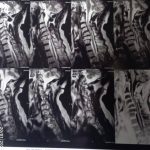

حيث استقبل المستشفى مريضًا يبلغ من العمر 70 عامًا، كان يعاني من ضعف تام وشلل كامل بالأطراف الأربعة، مع فقدان شبه كامل للتحكم في البول والبراز، وذلك على خلفية ادعاء التعرض للسقوط. وبإجراء الفحوصات الطبية والأشعات اللازمة، تبين إصابة المريض بانزلاق غضروفي عنقي متعدد على أربعة مستويات،

ما أدى إلى حدوث كدمة بالحبل الشوكي وضيق كامل بالقناة الشوكية العنقية، وهي من الحالات شديدة الخطورة التي تستدعي تدخلاً جراحيًا دقيقًا وعاجلًا.

وعلى الفور تم تجهيز الحالة طبيًا من خلال إجراء جميع الفحوصات والتحاليل اللازمة، قبل أن يخضع المريض لجراحة ميكروسكوبية دقيقة ومعقدة، تم خلالها استئصال الغضاريف المنزلقـة، وتركيب أقفاص عنقية مثبتة بدعامات ذاتية (Stand-alone) على أربعة مستويات، وذلك باحترافية عالية، مع خروج المريض من غرفة العمليات في حالة مستقرة وآمنة.